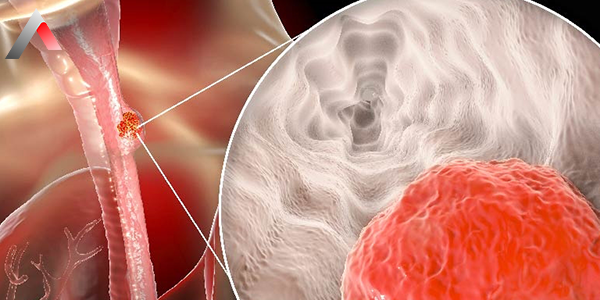

Özofagus kanseri, ağız yoluyla alınan besinlerin mideye iletilmesini sağlayan ve yaklaşık 25-30 cm uzunluğundaki kaslı bir tüp olan yemek borusunun (özofagus) iç yüzeyindeki hücrelerin kontrolsüz çoğalmasıyla başlar. Tıbbi literatürde bu hastalığın en etkili ve kesin tedavi yöntemi özofagus kanseri ameliyatı, yani özofagektomi prosedürüdür. Erken ve orta evre vakalarda uygulanan cerrahi müdahale, hastalığı tamamen ortadan kaldırmayı hedefleyen "küratif" bir yaklaşım sunar.

Yemek borusu kanseri sinsi ilerleyen bir hastalık olup, en belirgin semptomu olan disfaji (yutma güçlüğü) ortaya çıktığında genellikle tümör yemek borusu kanalını daraltmış durumdadır. Cerrahinin temel amaçları şunlardır: